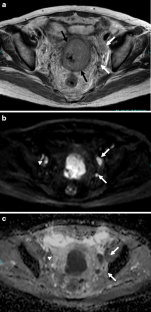

Fig. 5a–c